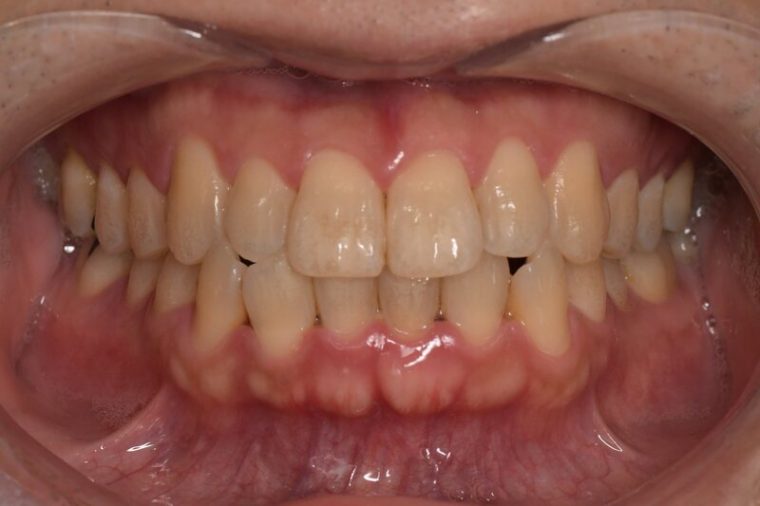

Before

症例

after

基本情報

年齢・性別 52歳・男性

主訴 主訴:久しぶりの歯医者なので歯石をとってほしい

治療部位:全顎

治療内容 1.歯磨き指導、歯肉縁上の歯石除去

2.歯磨きの確認、指導(磨けるようになるまで)

3.歯磨きの確認、指導、歯肉縁下の歯石除去(SRP)

4.PMTC

5.再評価、歯磨きの確認、指導

治療期間 1日

治療費 合計17,560円

・内訳

1、歯周基本検査・歯磨き指導、縁上スケーリング:1,800円

2、歯周精密検査・SRP(スケーリング・ルートプレーニング)、歯磨き指導:2,130円

3、SRP、歯磨き指導:3回(1,530円×3回)

4、PMTC、全顎再スケーリング、歯磨き指導:5,500円(自費診療)+1,260円

5、再評価(歯周精密検査)、歯磨き指導:2,280円

※PMTC以外、保険診療3割負担

(2023年5月現在現在)

リスク・副作用 ・毎日の歯磨きが不十分だと歯石を除去しても再度歯石がついてしまう

・最初は歯磨きのときに出血してくることがあるが、細菌が減って歯茎が引き締まってくると徐々に出血は落ち着いてくるため痛みがなければ辛抱強く磨いてもらう

・歯周病は時間をかけて静かに進行する病気なので、歯周病を治すにはそれなりに期間がかかる、すぐには治らない

・歯ぐきが引き締まると歯茎が下がり歯間に隙間ができる可能性がある

治療方針 一時的な治癒ではなく、将来的にこの治療が活かされるよう、患者さん自身である程度自己管理ができるようになることを目標とした

特記事項 ふつうのブラシと電動歯ブラシ使用(ブラウン丸型使)

歯間ブラシを1日1回は最低でも使って頂いた

担当者所見 あまり器用な方ではなかったため、決まったところがいつも磨けず奥歯に歯間ブラシがなかなか入れられませんでしたが、歯間ブラシのサイズを変えてみたり、内側から入れてみたりと試行錯誤してなんとかある程度磨けるようになりました。

その結果、出血が100%から7%へ激減することができました。

ただSRPをしただけではここまでの結果は出なかったと思います。

それほど日々のセルフケアが重要だということを再認識しました。

歯周ポケットが残っている部位、出血がある部位に関しては引き続き歯磨きを念入りに行なってもらう。